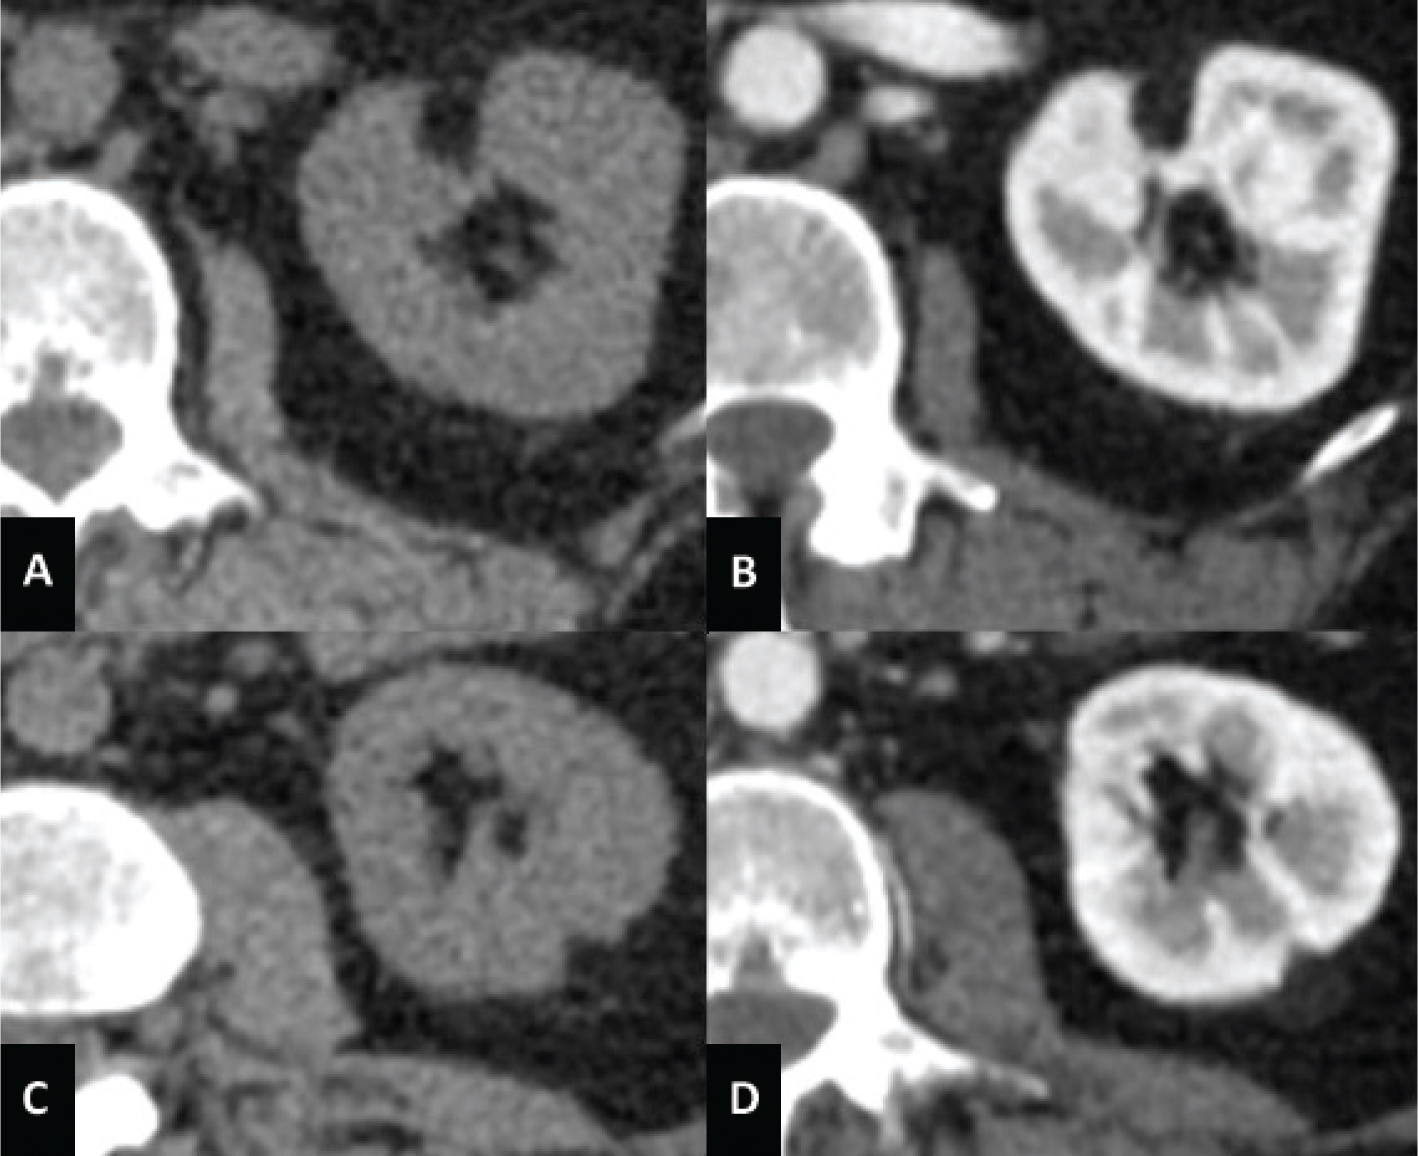

Classic AML is a subtype of triphasic AML. The typical characteristic of classic AML is the presence of abundant adipose tissue (11). This AML almost always appears markedly hyperechoic compared to the renal parenchyma. In addition, 21–33% of AMLs smaller than 3 cm show acoustic shadowing (58, 59). The fat present in AML can be identified on unenhanced CT with a region of interest (ROI) showing an attenuation less than −10 HU (Figure 3) (50, 60, 61). The CT features of classic AML vary due to variable amounts of the three components present in the lesion (11). Furthermore, intralesional hemorrhage may be present, especially in tumors larger than 4 cm (62). MRI can be used to diagnose AML also by detecting fat cells; India ink artifact visible with a loss of signal at the boundary between the mass and the renal parenchyma is indicative of AML (52).

Fig 3

Figure 3. Unenhanced CT axial scan of the abdomen (A and C) and CT of the abdomen during arterious phase (B and D) of a 53-year-old woman showing the presence of classic AMLs, recognizable by the adipose component of the lesion.